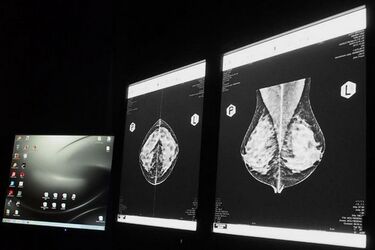

Mammografia to radiologiczna metoda badania piersi u kobiet. Polega na wykonaniu serii zdjęć gruczołu przy użyciu promieni rentgenowskich. To sposób na wczesne rozpoznanie raka piersi. Wykrycie tej choroby w stadium ograniczonym daje szansę na wyleczenie. Panie powinny pamiętać, że im mniejsza zmiana w piersi, tym łatwiej ją wyleczyć. Mammografia jest bezpłatna dla kobiet w wieku 50-69 lat, które w ciągu ostatnich 2 lat nie robiły tego badania lub otrzymały pisemne wskazanie (z powodu obciążenia genetycznego) do zrobienia go po upływie 12 miesięcy. Panie zainteresowane tym tematem, w najbliższym czasie, mogą skorzystać i przebadań się w mammobusach. Do końca lutego stacjonowały one będą w takich podlaskich miastach i miejscowościach jak: Zabłudów, Łapy, Siemiatycze, Bielsk Podlaski, Hajnówka, Drohiczyn, Ciechanowiec, Zambrów, Wysokie Mazowieckie, Kolno, Augustów, Suwałki. Szczegółowy wykaz dat i adresów można znaleźć na stronie internetowej Podlaskiego Oddziału Wojewódzkiego Narodowego Funduszu Zdrowia. Przy czym warto wiedzieć, że osoby, które z rożnych powodów nie zgłoszą się, a zależy im na badaniu (także bezpłatnym), mogą wykonać je również w punkcie stacjonarnym. Opcję taką proponuje np. przychodnia Wirtus Plus, która znajduje się przy ul. Siewnej 2 w Białymstoku. Można zgłaszać się telefonicznie - 85 676 03 32 lub 85 676 13 22. Trzeba jednak pamiętać o zabraniu dowodu osobistego oraz zdjęcia lub płytki z poprzedniej mammografii.